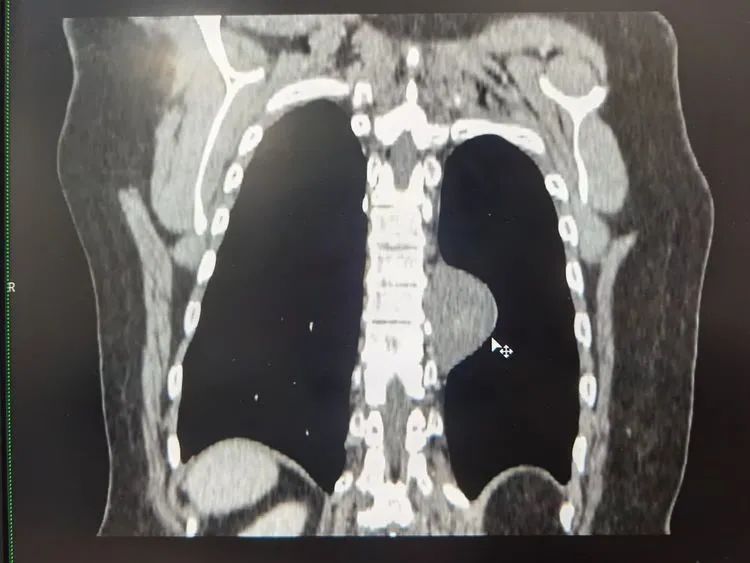

患者胸部增强CT扫描提示:见其左后纵隔旁占位,考虑神经源性肿瘤可能性大。据了解,神经源肿瘤是纵隔内常见的肿瘤之一,占纵隔肿瘤的15%~30%,大部分为良性。目前的病因及发病机制尚不明确,女性患者略多于男性,任何年龄都可以发生,但儿童神经源肿瘤恶性率较高(50%),成人在10%以下。纵隔神经源性肿瘤多发于后纵隔,多数患者无症状。部分患者可有咳嗽、气短、胸痛等症状,治疗以手术为主,放化疗为辅,其预后与肿瘤的良恶性密切相关。

结合各项检查,确诊孙女士系左后纵隔肿瘤。影像见肿块大小约45mm*36mm*48mm,术前无肺功能障碍,集团胸心外科医疗中心高涛涛院长会诊后,决定为其在全麻下行单孔胸腔镜下左侧胸纵隔占位切除术+肋间神经阻滞术。